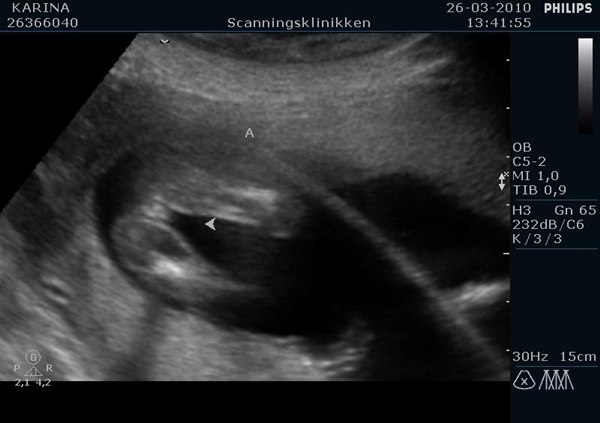

Men det der ligger i det, er at kønnet er udviklet, men at man på scanningen ikke kan kende forskel, medmindre barnet ligger helt perfekt, og så skal man være ekstrem erfaren for at se forskel, da skamlæber og pung ligner hinanden.

Så ja, man kan godt, men chancen for at den lille ligger rigtigt og at de har ret i hvad de tror de ser, er meget lille.